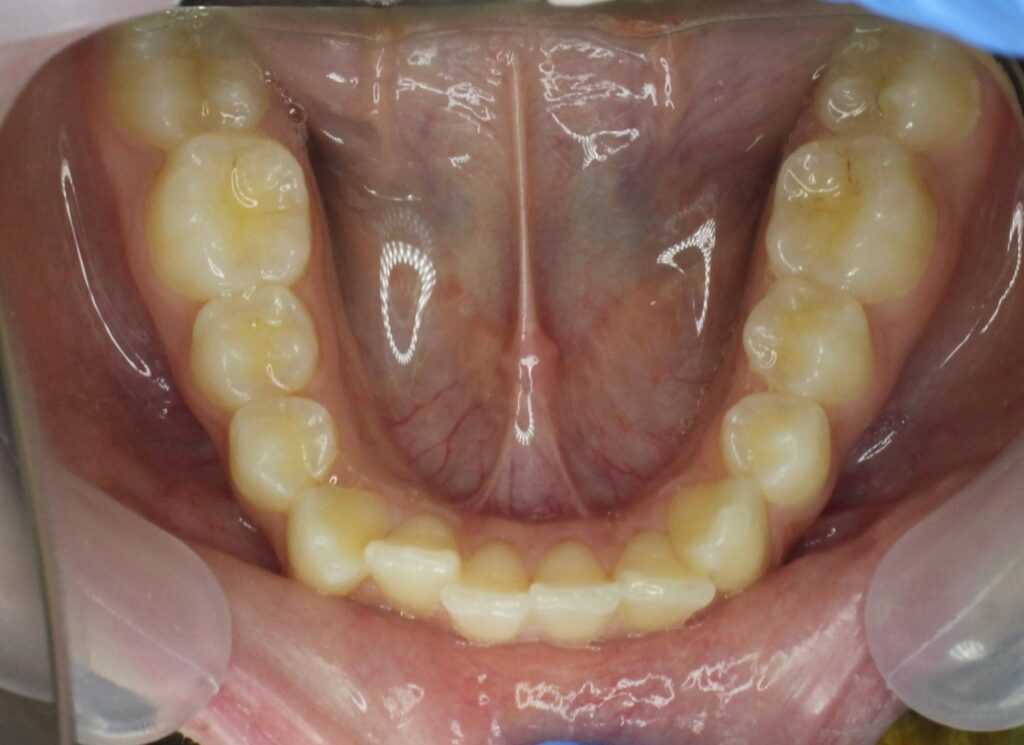

Ситуация до лечения

Жалобы: Пациентка обратилась с жалобами на неровное положение передних зубов.

Диагноз: дистальный прикус, сужение верхнего и нижнего зубных рядов, скученность фронтальной группы зубов на верхней и нижней челюсти.

пациент до лечения брекетами